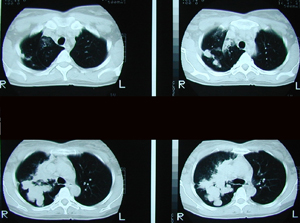

Εικόνα 2

Αξονική τομογραφία θώρακος που δείχνει μάζα εκ μαλακών μορίων στον δεξιό άνω λοβό με επέκταση προς την πύλη. Πρόκειται για μάζα με ανώμαλα όρια και πολυλοβωτή μορφολογία.